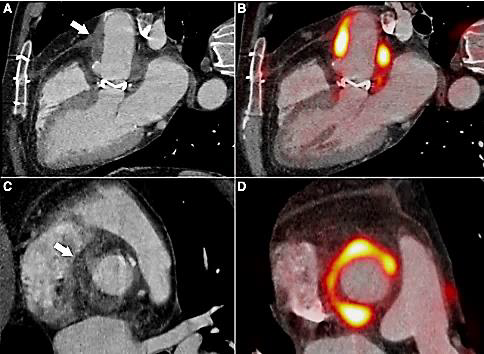

Culturas de escarro, de sangue e de urina coletadas na admissão e antes da antibioticoterapia resultaram negativas. Solicitado ecocardiograma transtorácico que demonstrou válvula normofuncionante sem outras alterações, achado este confirmado por um ecocardiograma transesofágico posteriormente. Durante evolução na enfermaria, paciente passou a queixar-se de fraqueza em todo o hemicorpo esquerdo, sendo prontamente encaminhado à tomografia computadorizada de crânio que não demonstrou alterações. Paciente recuperou espontaneamente a força cerca de quatro horas após. Diante da principal suspeita, foi solicitado o exame demonstrado na Figura 8.

--------------Figura 8. Tomografia por emissão de pósitrons do coração